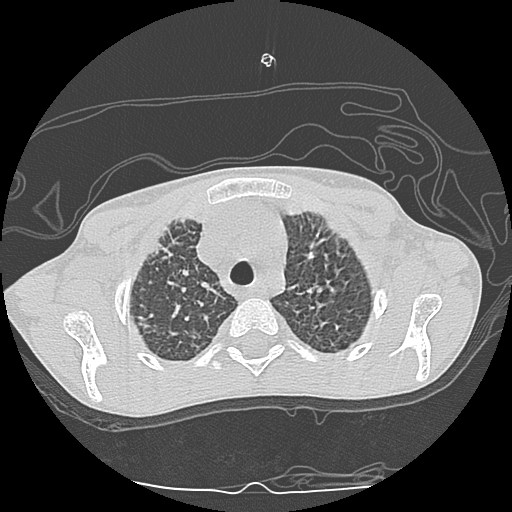

- Computerized tomography (CT) of chest.

| CT3 | CT4 | CT5 |

| CT1 | CT2 |